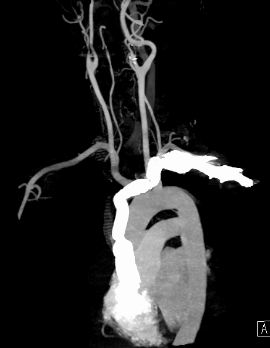

術後MRI影像,人工血管正常運作